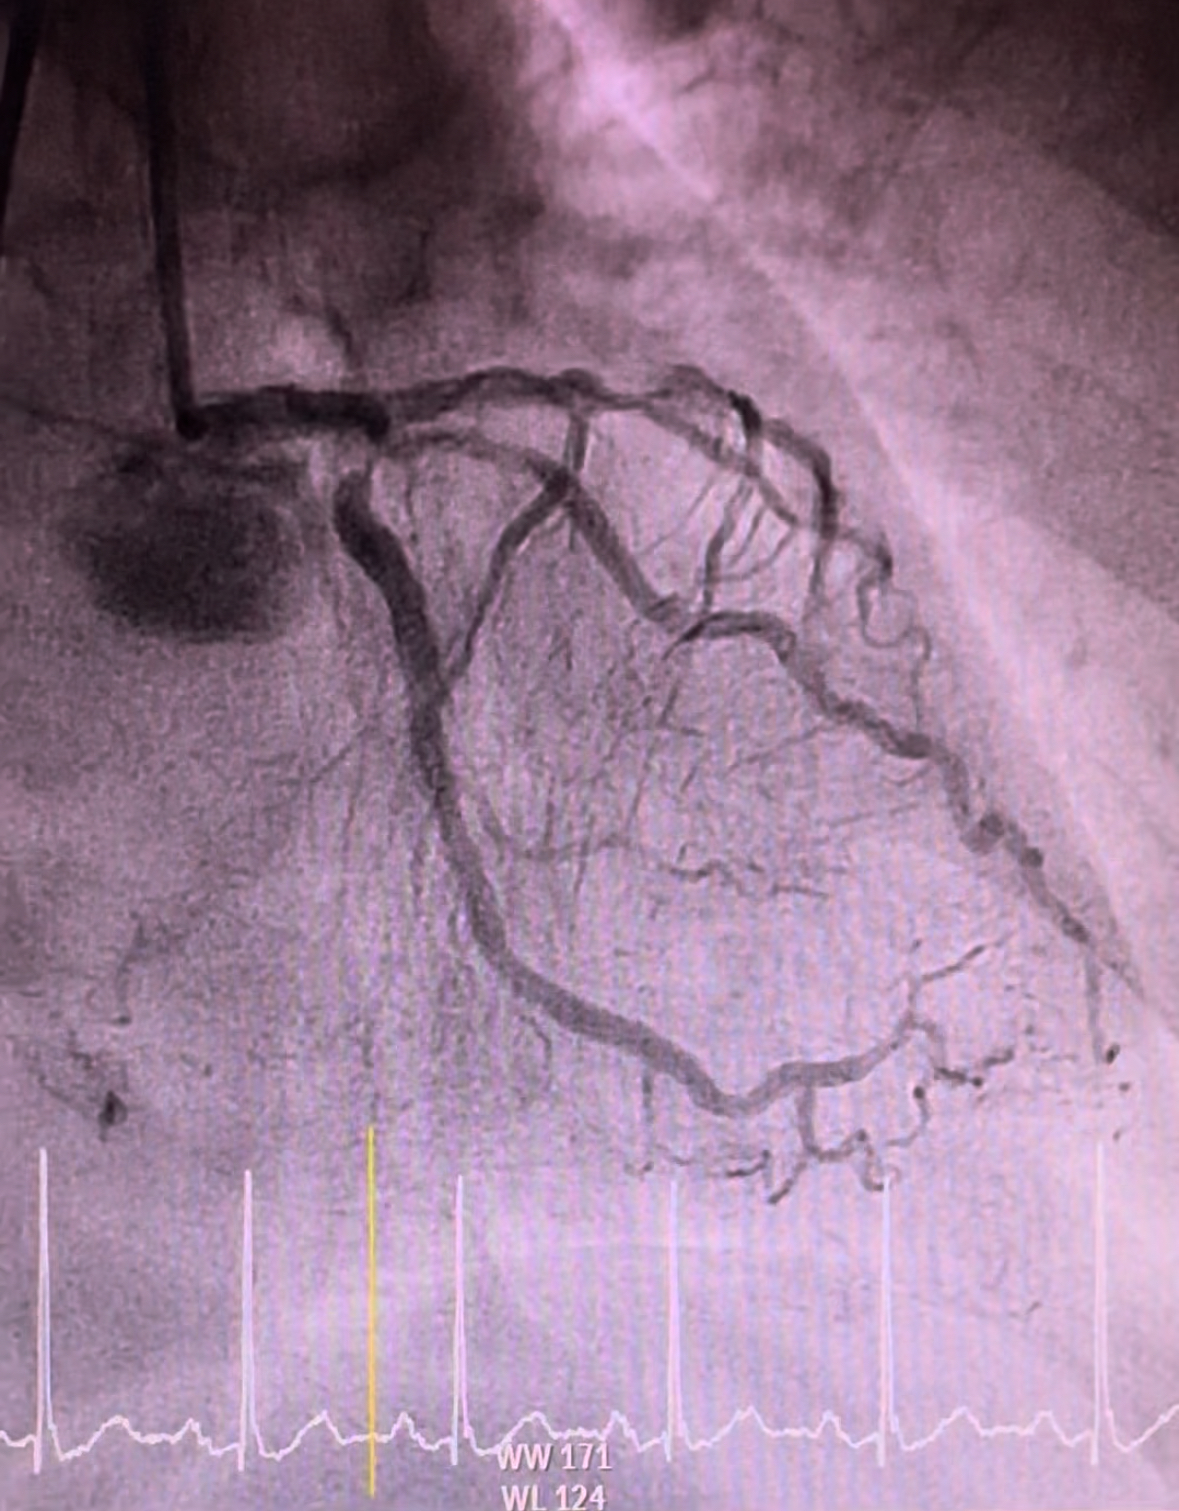

Coronary angiogram demonstrated smooth left main, 90% stenosis in the proximal left circumflex, 99% focal stenosis with severe calcification at mid LAD, followed by mild diffuse plaque until the distal end, and 90% stenosis at ostial D1. Right coronary was calcified with 80% stenosis at the proximal segment, 90% stenosis at the mid segment, and CTO at the distal segment. Discussion was held with cardiothoracic surgeons in which CABG was viewed incompatible.